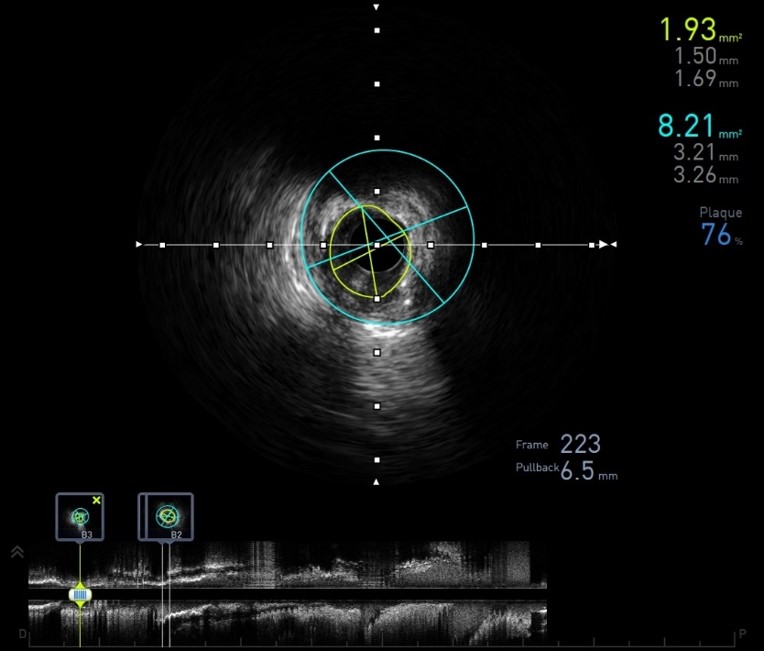

Ultrasonido intravascular (IVUS)

El Ultrasonido Intravascular (IVUS) es un complemento de la coronariografía. Consiste en un pequeño catéter que transporta un transductor de ultrasonido miniaturizado, el cual permite ver “in vivo” la pared de los vasos y las alteraciones que la aterosclerosis produce en los mismos. Por lo tanto, con este método podemos “ver” la enfermedad coronaria y no inferir su presencia según el grado de irregularidades que se producen en el “lumenograma” de una angiografía.

El ultrasonido intravascular permite detectar estadíos precoces de la enfermedad coronaria, los que son totalmente “silentes” en la angiografía. Así es como esta modalidad diagnóstica no reemplaza a la coronariografía, sino que son complementarios y suman información para el diagnóstico y la toma de decisiones.

Con el advenimiento de las nuevas tecnologías, el IVUS ha incorporado la posibilidad de caracterizar histológicamente la placa ateromatosa (histología virtual o caracterización tisular), permitiendo detectar placas “más peligrosas o vulnerables” las cuales podrían beneficiarse con un tratamiento médico/intervencionista más agresivo.

La utilidad del IVUS está ampliamente validada por numerosos estudios clínicos, que lo han impuesto como método de referencia en distintas situaciones: valoración de lesiones dudosas o de obstrucciones de grado moderado, “guiar” procedimientos complejos (angioplastia de tronco coronario izquierdo, reestenosis intra stent, oclusiones totales crónicas, bifurcaciones y disecciones coronarias), optimización del implante de stents farmacoactivos o “liberadores de drogas”.

Este método nos permite: confirmar la severidad de la lesión, medir con mayor exactitud el tamaño del vaso y analizar los segmentos de referencia, seleccionar correctamente el stent a utilizar ya sea en longitud como en diámetros, analizar la composición y morfología de la placa a tratar y finalmente optimizar el correcto implante del stent.